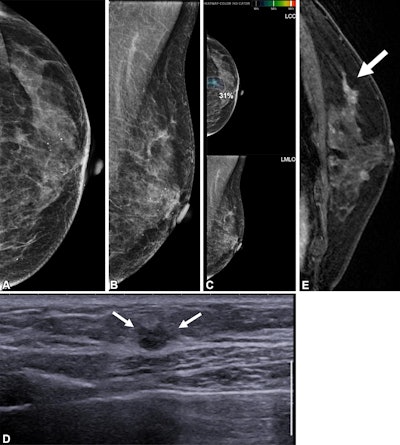

Images depict a 65-year-old patient with contralateral second breast cancer 6.3 years after right mastectomy. (A) Left craniocaudal and (B) mediolateral oblique mammograms assessed as benign. (C) The AI algorithm outlined a lesion with a score of 31 on the craniocaudal view. (D) A supplemental axial ultrasound scan, which was obtained on the same day as the mammogram, shows an irregular hypoechoic mass (arrows) in the left upper central breast. (E) Preoperative sagittal contrast-enhanced T1-weighted MRI scan shows the corresponding enhancing mass (arrow) in the left upper center. The mass was proven to be ductal carcinoma in situ.RSNA